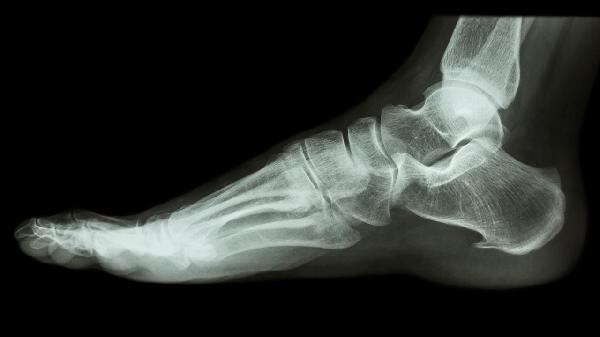

足舟骨突出疼痛可能与足舟骨发育异常、足部外伤、足弓塌陷、关节炎、痛风等因素有关。足舟骨是足部内侧的重要骨骼,其突出疼痛通常表现为局部压痛、肿胀或活动受限,建议及时就医明确诊断。

部分人群存在先天性足舟骨形态异常或副舟骨,这类结构变异可能导致局部应力集中,长期行走或运动时引发无菌性炎症。患者常表现为足内侧隆起伴间歇性钝痛,X线检查可明确诊断。急性期需减少负重活动,遵医嘱使用双氯芬酸钠缓释片、塞来昔布胶囊等抗炎镇痛药物,慢性期可通过定制矫形鞋垫缓解症状。

足部扭伤或直接撞击可能导致足舟骨骨折、骨膜损伤,表现为突发剧痛伴皮下淤血。这类损伤常发生于运动时足部内翻扭伤,需通过CT检查排除隐匿性骨折。初期应制动冰敷,后期可遵医嘱使用伤科接骨片、云南白药气雾剂等促进修复,严重骨折需石膏固定6-8周。

后天性扁平足患者因胫后肌腱功能减退,导致足弓支撑力下降,足舟骨被迫承受更大压力而突出疼痛。典型表现为久站后足部酸胀,内侧可见明显骨性凸起。建议穿戴足弓支撑鞋,配合胫后肌强化训练,疼痛明显时可短期使用洛索洛芬钠贴剂缓解症状。